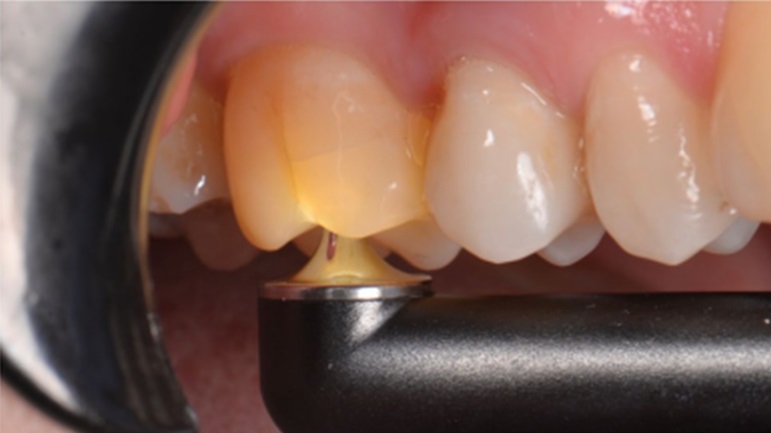

Diagnóstico y tratamiento: Identificar con precisión el síndrome del diente fisurado puede involucrar pruebas como radiografías, examen clínico y evaluación táctil con herramientas dentales específicas. El tratamiento odontológico varía dependiendo de la severidad de la fisura, se debe definir correctamente la ubicación, profundidad y extensión de la grieta para seleccionar y realizar un protocolo restaurativo adecuado. De este modo, mediante un tratamiento restaurador eficaz, se puede limitar la propagación de la fractura y la posible enfermedad pulpar asociada. Abarcando desde restauraciones simples, incrustaciones hasta tratamientos de conducto o incluso extracción en situaciones más críticas donde la fisura llega hasta la raíz dentaria.